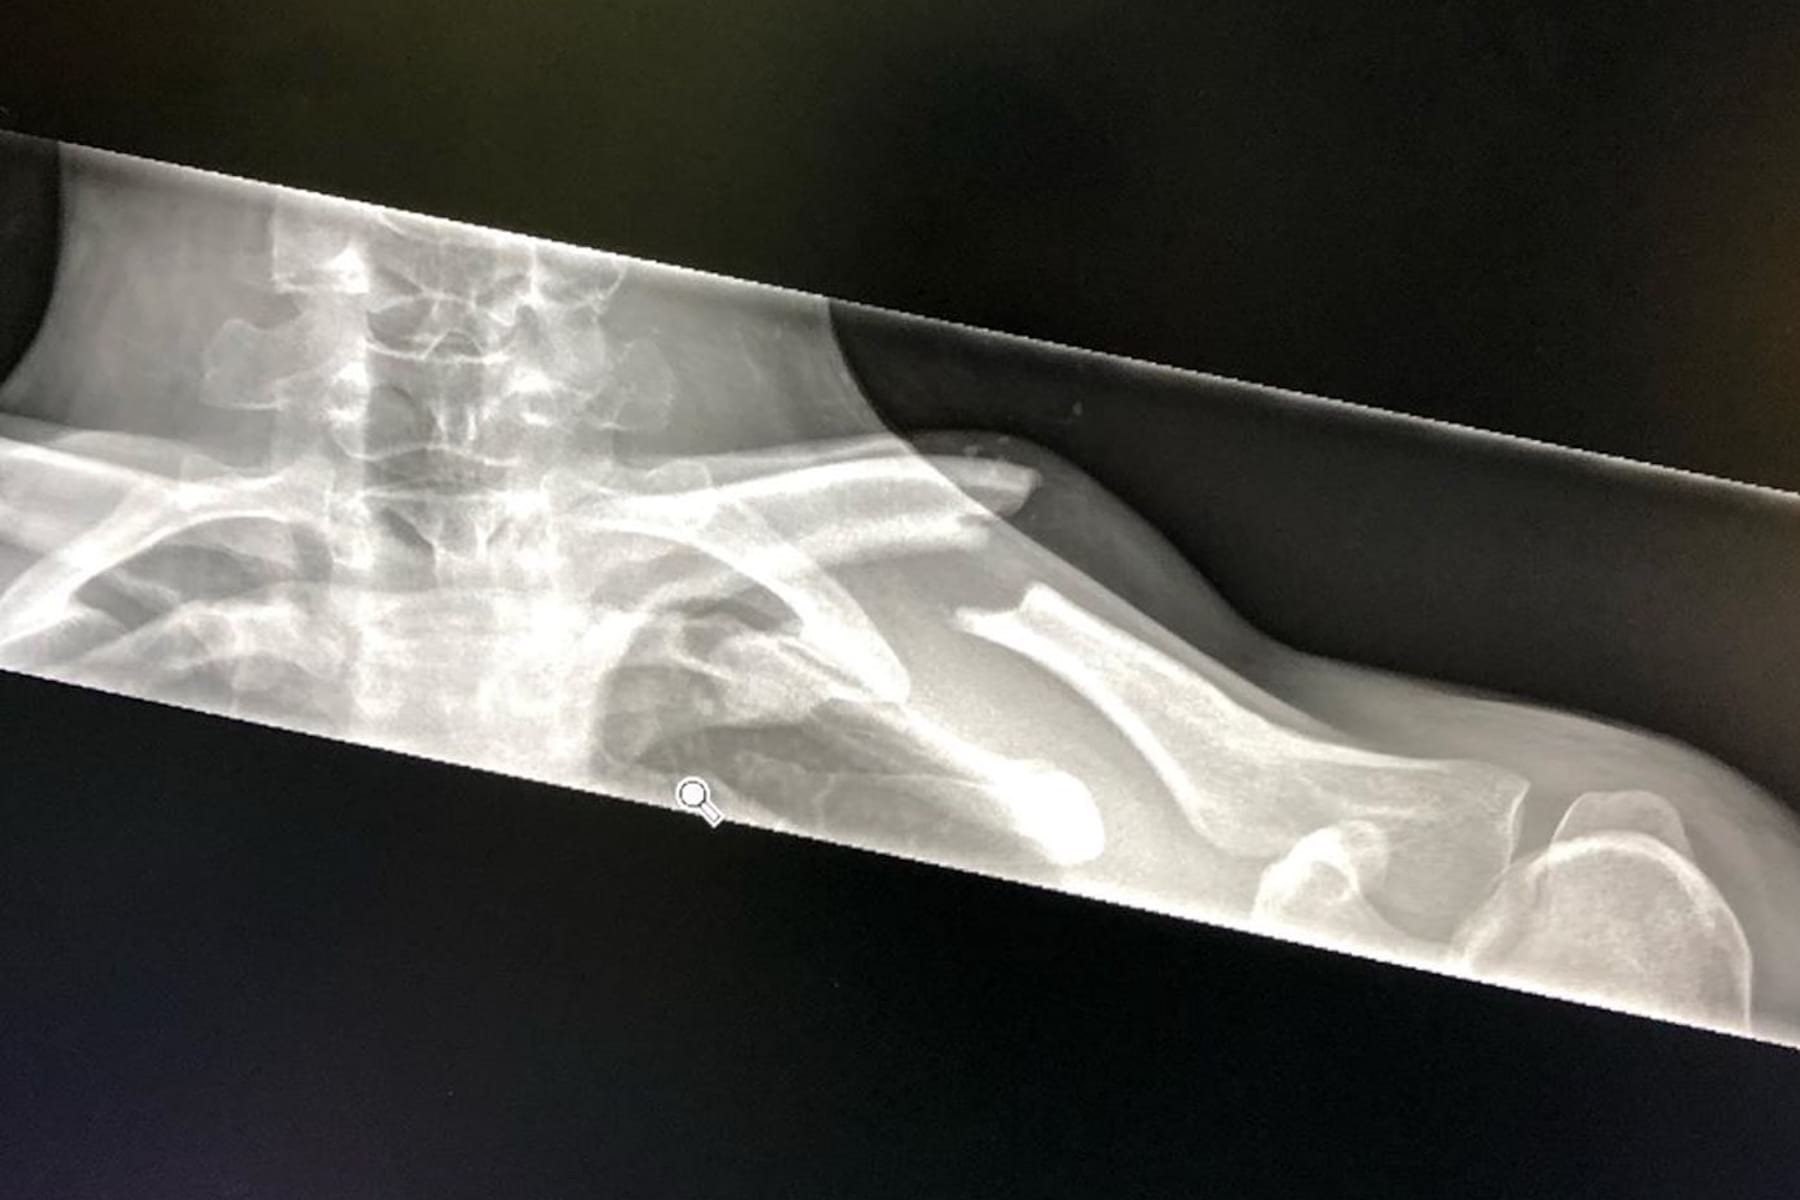

“This post is a little hard for me to write but I felt like I needed to keep you all up to date. I didn’t get to enjoy the #1 plate for very long as I had a real bad crash in my first run this morning in the top section. The first thing to hit was my right shoulder on a rock. I train real hard to avoid as much damage as possible when something like this happens & until now I’ve been pretty bullet proof, but this time it was a little harder for me to get back up! For now all I know from an X-ray is that I’ve torn my AC joint which has separated my collarbone from my shoulder. I’ve now got a new goal at hand and that’s to get back riding and racing my bike ASAP! 🙏🏻 I’ll be getting an MRI and seeing a specialist to check there is no further damage🤞🏻I will keep you all updated! ❤️ I didn’t even get a chance to wear the leaders jersey 😂 until next time…. 🙏🏻 pics @maddogboris“